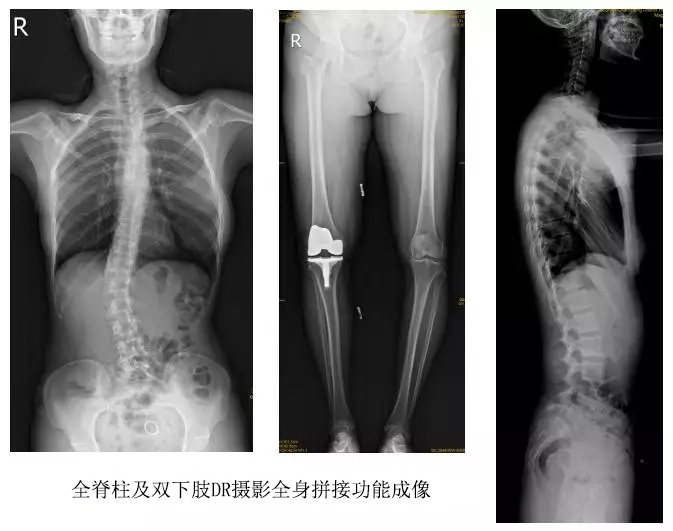

臨床在診治脊柱及下肢畸形時,往往采取矯正手術治療。這就需要在對其進行手術前后,拍攝全脊柱或全下肢的X光片作為診治依據,以便分析病情、制定手術方案和評估術后療效。目前大部分醫院使用的DR攝片機,因拍攝幅面受限,最大規格43cm,但成人的全脊柱長度一般約60cm,而全下肢更長,不能一次性拍攝出完整的全脊柱或全下肢的X光影像。以全脊柱攝片為例,各拍攝一張傳統的頸椎、胸椎、腰椎的X片雖然就能觀察到每個部位局部的側彎情況,但不能觀察到三者之間的連續性。因此傳統X光片在這類疾病診斷上存在著一定的缺陷,無法更精準有效地進行臨床診斷和治療。

以某院所攝X光片為例,對比傳統攝片與全身拼接功能的區別:

傳統X光片只能觀察每個部位的局部情況,無法在統一體上進行連續、全面的觀察,全脊柱及下肢全長片則能直觀的看到整體形變。通過DR全身拼接功能實現的完整成像,為診治脊柱及下肢畸形提供了完美的臨床影像依據,對臨床診斷、術前手術方案的制定和術后療效的評估等臨床應用具有十分重要的意義,有效滿足了此類疾病臨床診斷和治療的要求。